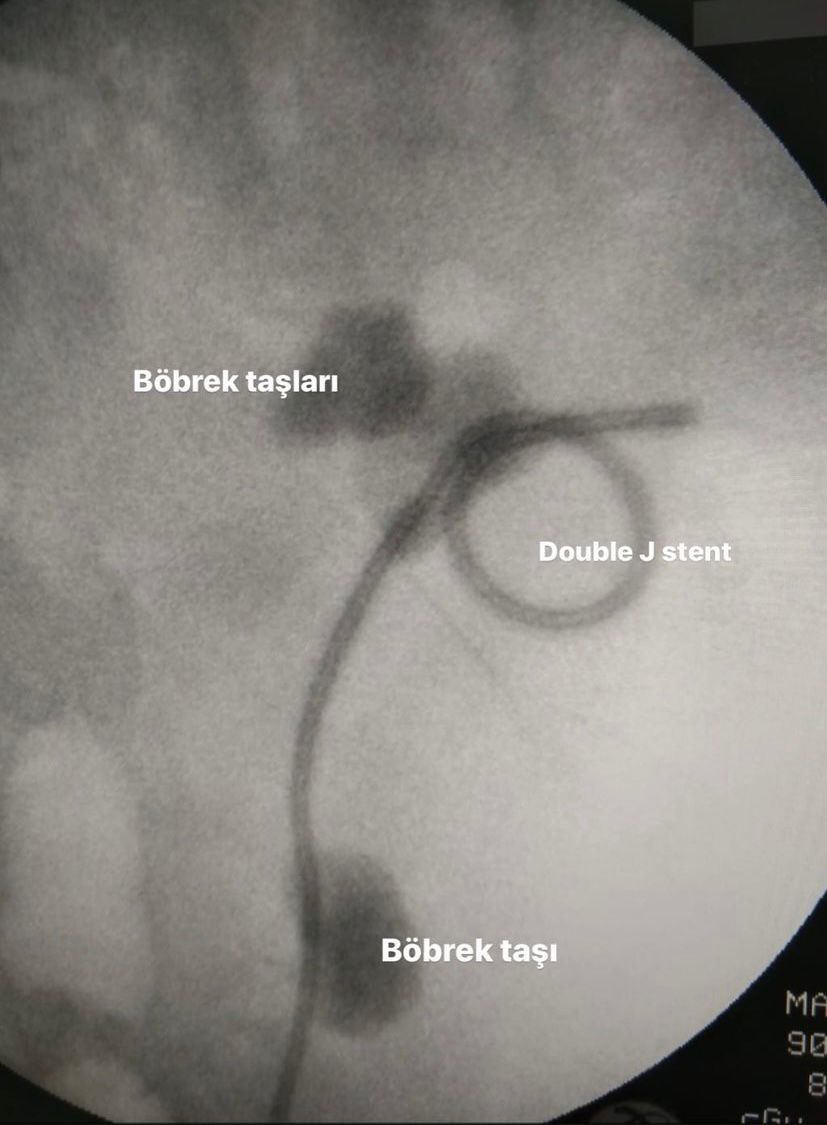

- Böbrek Taşı

Böbreğimde 47 milim taş vardı erhan bey kapalı ameliyatla taşlarımi kırıp aldı bandırmada böyle bir doktor olduğu için çok şanslıyız. Kendisi mükemmel bir doktor tavsiye ederim